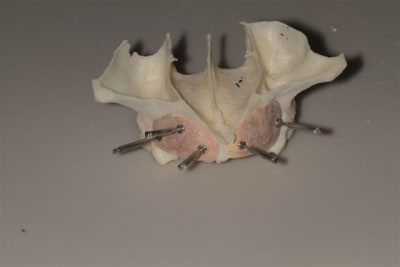

La première diapo est un essai pour justifier le concept (os non destiné à une utilisation greffe)

la deuxième est "tapée" dans une tête de femur de mauvais qualité (rejetée)

la troisième et suivante ce sont "les greffons" définitifs.